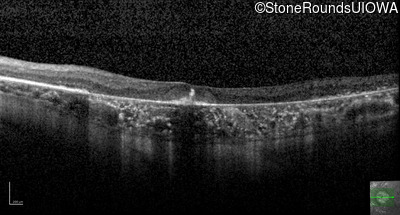

Age at visit: 63 years

This 63 year old woman has had normal vision for most of her life, but recently developed difficulty seeing in dim light.

Diagnosis & molecular findings

AD Retinitis Pigmentosa SAG Cys147Phe TGT>TTT   AD